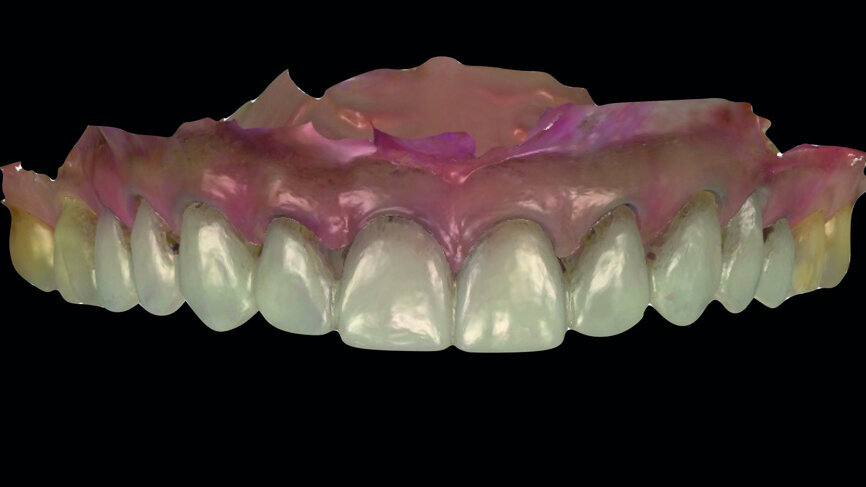

Fig. 13: Analogue workflow (refractory dies, built-up veneers, adjustments, staining/glazing).

Provisionalisation was executed digitally, using Telio CAD (Ivoclar Vivadent) in the Wieland Select CNC milling machine. The design was performed with the 3Shape DentalDesigner 2015 software (Figs. 12a & b). Two sets of final restorations were fabricated. The set of feldspathic veneers was fabricated on a stone model using IPS Style (Ivoclar Vivadent), while IPS Empress CAD Multi (Ivoclar Vivadent) was used for the digitalset (Figs. 13 & 14). Both sets were examined intraorally with a try-in paste to compare the optical properties of the feldspathic and the CAD/CAM veneers (Figs. 15a–c).